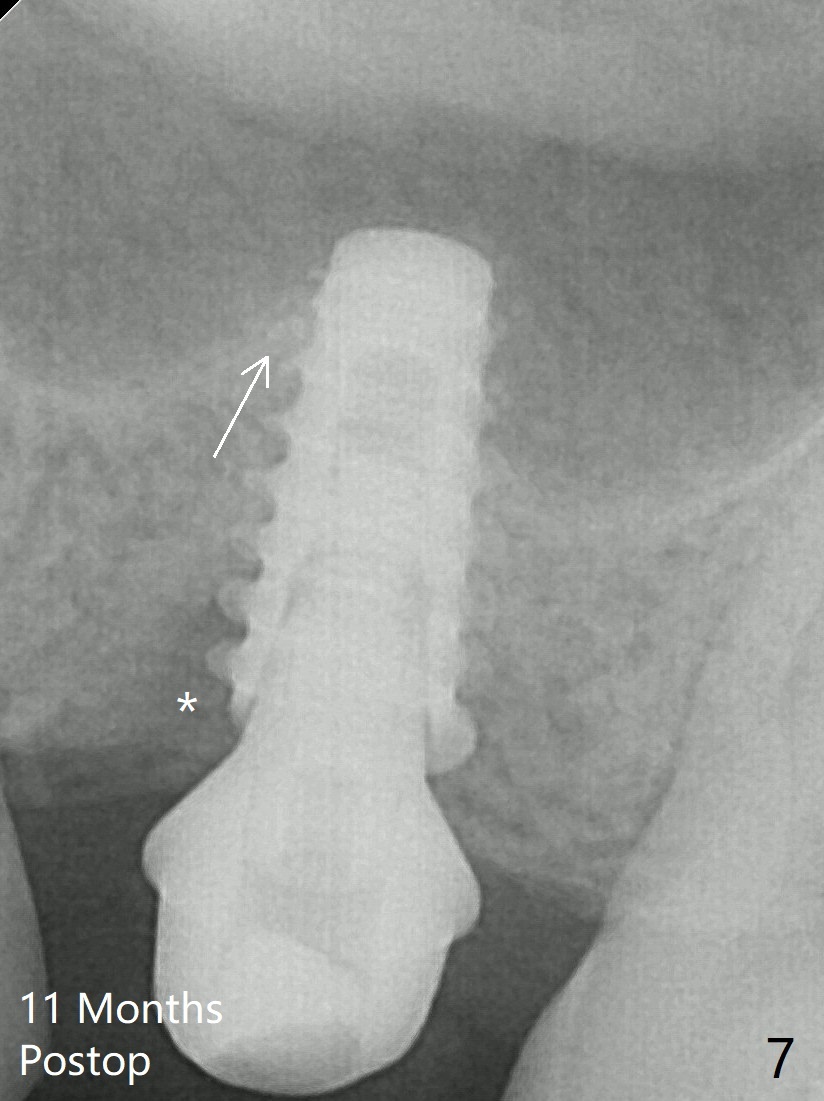

After insertion of a 4.5x11 mm dummy implant at 9 mm (35 Ncm; for further bone expansion), one piece of PRF plug and 1 piece of PRF membrane are pushed into the osteotomy, followed by allograft mixed with autogenous bone for sinus lift (*) and placement of a 5x9 mm implant (Fig.3,4 with insertion torque >50 Ncm). The implant appears to have been placed too deep. In fact a BW shows otherwise. There is mild bone resorption at the crest 11 months postop (Fig.7 *). Although the sinus lift with bone graft becomes less distinct, there is more implant/bone contact mesial (arrow). The bone resorption seems to be worse 8 months post cementation (Fig.8,9); in fact the abutment screw is loose. The gingiva is healthy.